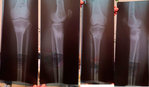

рентген в 3 месяца, после снятия аппаратов.

Советы: раз в пол года старайтесь принимать биодобавки (в основе Кальций, Магний), женщинам за 40...

После 40 у женщин в этом возрасте затухает гормональная функция и возникает опасность для костной системы – костная масса уменьшается с каждым годом почти на 1%. Необходима консультация врача гинеколога, который поможет подобрать гормоно- заместительную терапию для поддержания здорового баланса и продления молодости организму. 094f316296.gif

Вложения

IMG-20180218-WA0020.jpg